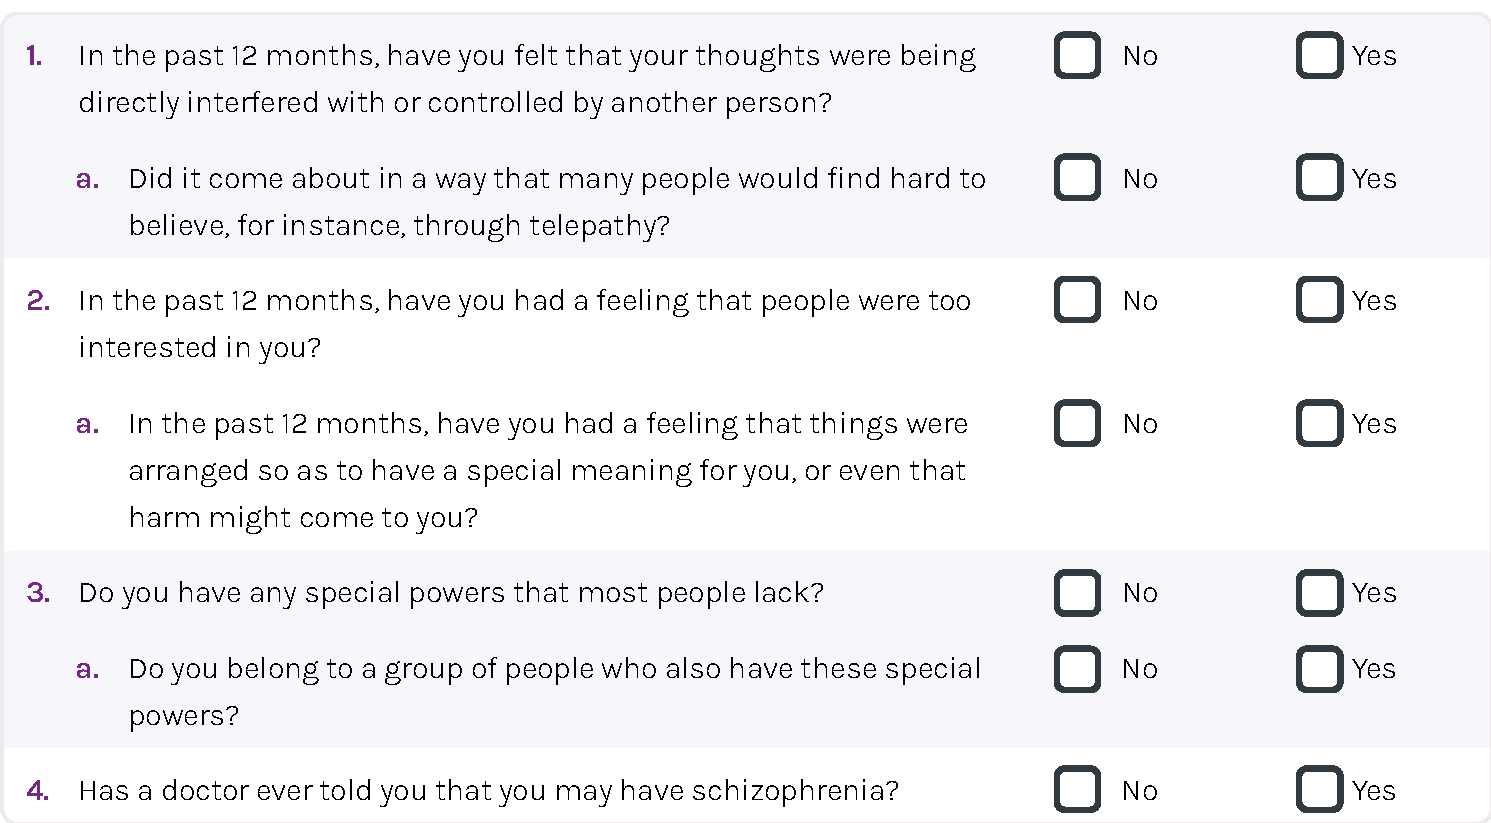

Psychosis Screener PS